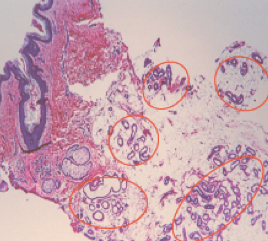

Эффект от процедуры длится всю жизнь, это связано с тем, что онтогенез потовых желез проходит только в эмбриональном периоде, так что они не регенерируют после рождения (рис. 6; Hai-Hong Li et al. 2006).

Рис.6(a). Данные гистологии. Эккриновые и апокриновые железы до процедуры.

лечение гипергидроза на аппарате MiraDry

Рис.6(b). Данные гистологии. Завершенные некроз желез спустя 10 дней после процедуры.

Рис.6(c). Данные гистологии. Отсутствие потовых желез через 6 месяцев после первой процедуры.